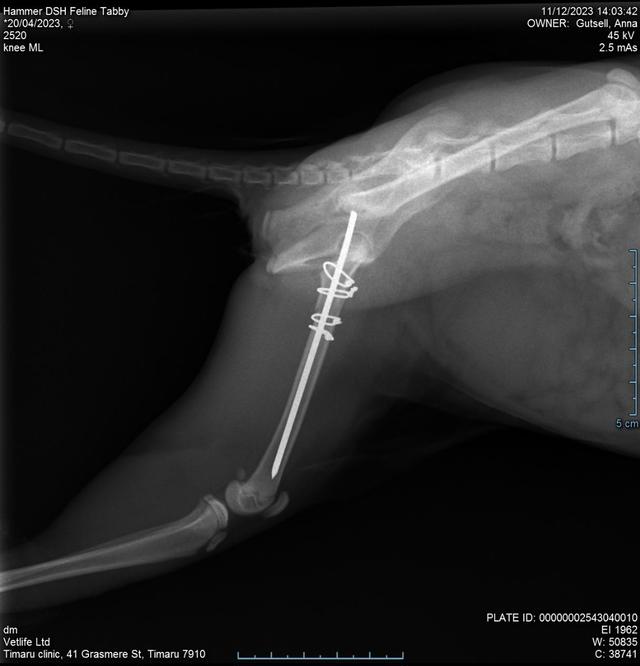

Hammer is home post op  13 December 2023

We have the best relationship with our vets not only have other clinics called me to see how Hammer is doing but they have done an amazing job on a very tricky femoral repair on a very small cat. Thank you so much to all that have sent well wishes or donated this is appreciated beyond words her vetbill was slightly higher than estimated but she has an amazing chance to heal now. We will have follow up appointments and more xrays I'm around 6 weeks to check on everything now she has 6 weeks of crate time to heal.